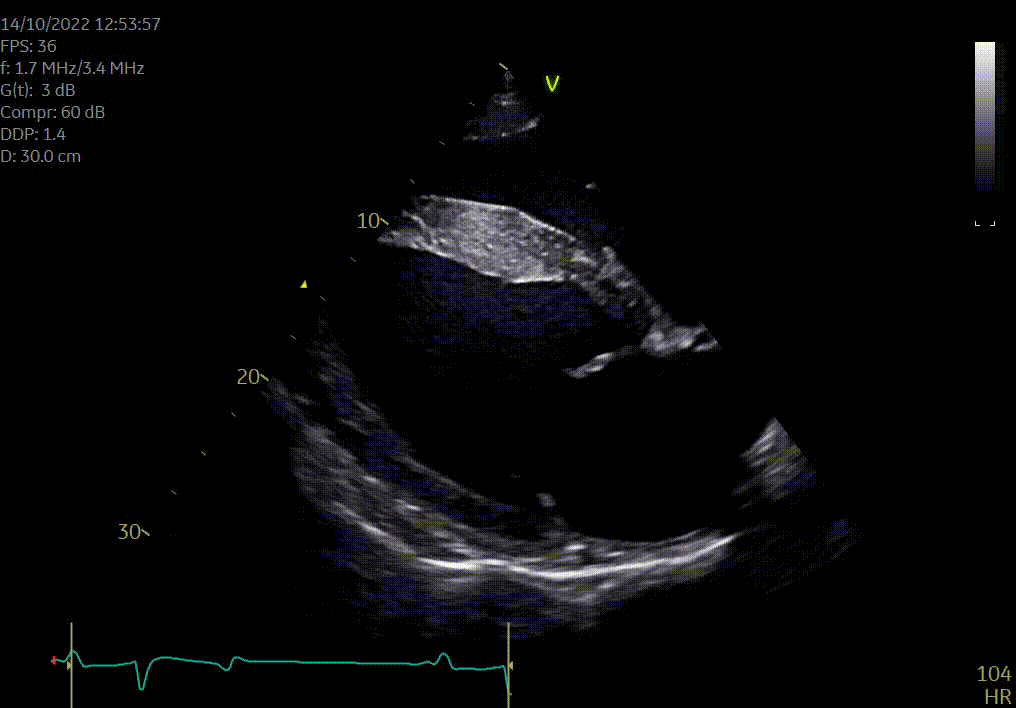

Heeft uw paard een hartruis? Dan is het aanbevolen om een echocardiografie (hartonderzoek) en een inspanningstest met elektrocardiogram (EKG) te laten uitvoeren. Zo kunnen we beoordelen of het veilig is om uw paard te berijden. Een hartruis is namelijk niet altijd een probleem. Met een echocardiografie onderzoeken we of het hart een normale structuur en werking heeft en bepalen we de ernst van eventuele klepafwijkingen.

Voor een uitgebreid hartonderzoek hoeft u niet langer naar een kliniek. Zowel de echocardiografie als de inspanningstest met elektrocardiogram kunnen eenvoudig bij u ter plaatse worden uitgevoerd.

Wij voeren hartonderzoeken uit op locatie in heel België, Nederland, Frankrijk, Duitsland en Luxemburg.

Hartonderzoek - Echocardiografie - Electrocardiografie (EKG)